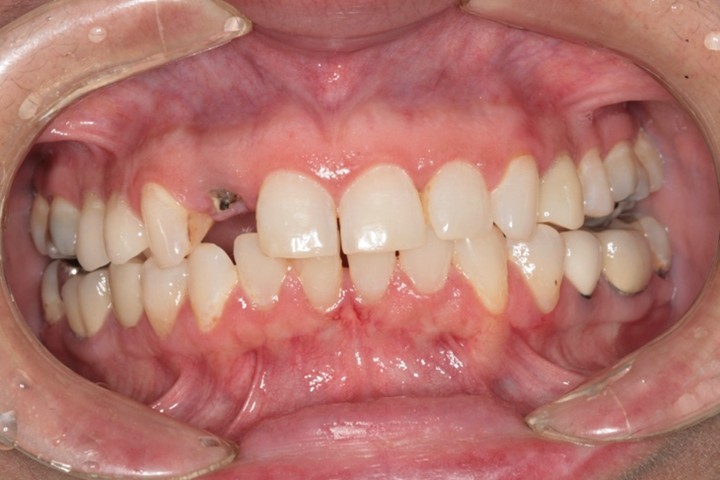

抜歯即時インプラント埋入

| 年代 | 56歳 |

|---|---|

| 性別 | 女性 |

| 治療内容 | 高度齲蝕歯の抜歯と抜歯即時インプラント埋入1本、上顎前歯の審美補綴(ジルコニアセラミック冠)3本 上額前歯1本の抜歯即時インプラント。上顎前歯3歯のジルコニアセラミックによる歯冠補綴 レントゲン診断、CT診断、補綴シミュレーション、血液検査、心電図、サージカルガイド製作、静脈内鎮静法、抜歯、インプラント埋入、暫間補綴、印象・咬合採得、インプラント上部構造装着、ジルコニアセラミック冠装着、メインテナンス |

| 治療期間 | |

| リスク | 術中の不可抗力によるトラブル(出血など)、術後注意事項を守らないことによる疼痛、感染、上部構造装着後口腔内清掃を怠ったことによるインプラント周囲組織の炎症 |

| 副作用 | 治療後の口腔内清掃、及びメインテナンスを怠ったことによるインプラント周囲粘膜炎またはインプラント周囲炎 |

| 費用 | 1,056,000円(税込) (CT撮影診断、血液検査、心電図モニター、補綴シュミュレーション、治療用義歯、サージカルガイド製作、静脈内鎮静法、インプラント埋入、投薬、2次手術、印象・咬合採得、ジルコニアセラミック歯冠補綴、インプラント上部構造などを含む) |